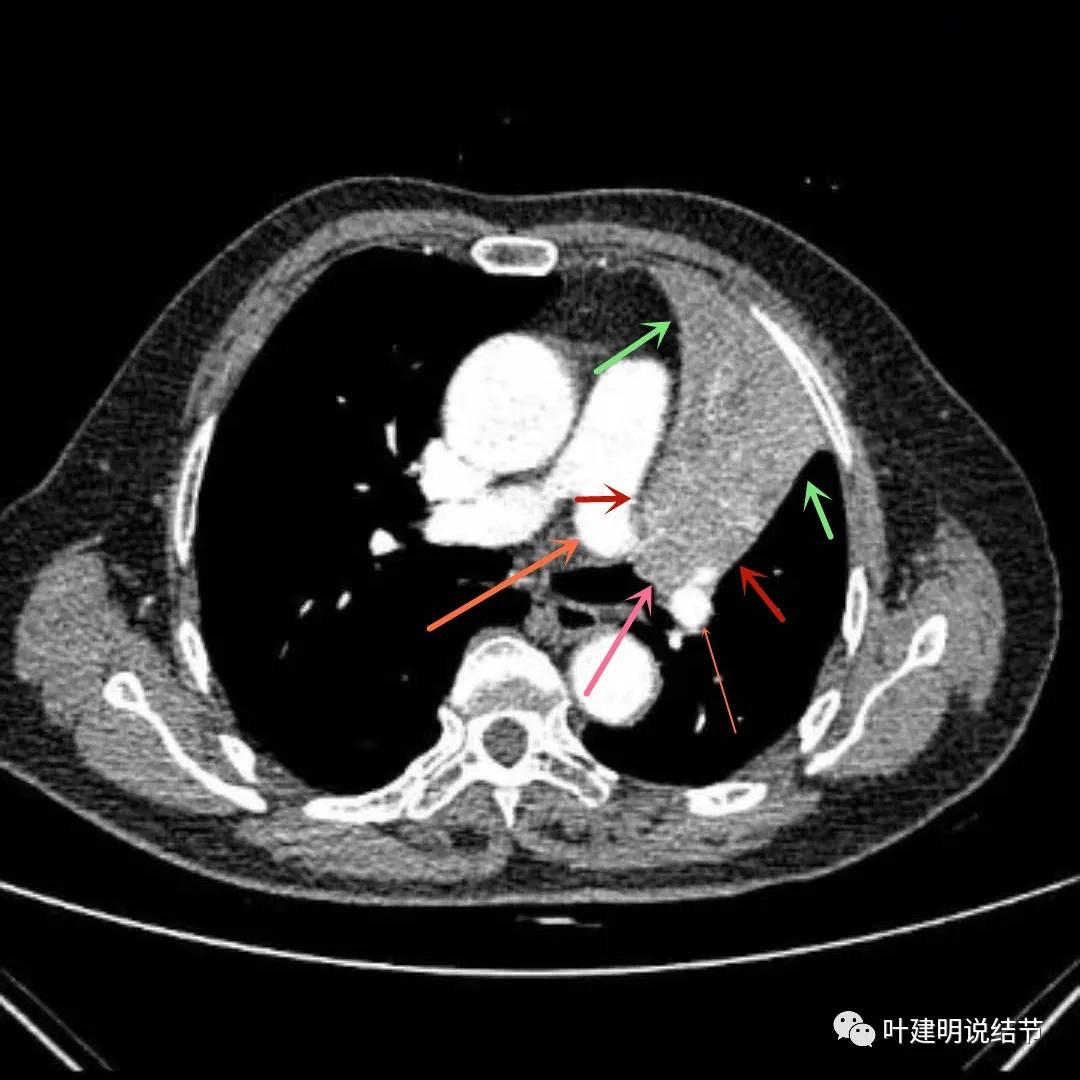

上图绿色箭头所指区域考虑为肺不张,红色示肿瘤处且有不均质与膨胀性,桔色箭头所指处显示肿瘤与肺动脉关系密切,考虑有侵犯肺动脉

上图绿色箭头所指区域考虑为肺不张,红色示肿瘤处且有不均质与膨胀性,桔色箭头所指处显示肿瘤与肺动脉关系密切,考虑有侵犯肺动脉。之所以肺动脉中间有软组织影,是因为肿瘤长到肺动脉与支气管之间的缝隙里,相当于血管是跨在肿瘤上,与肿瘤接触的这面是侵犯愈着的。